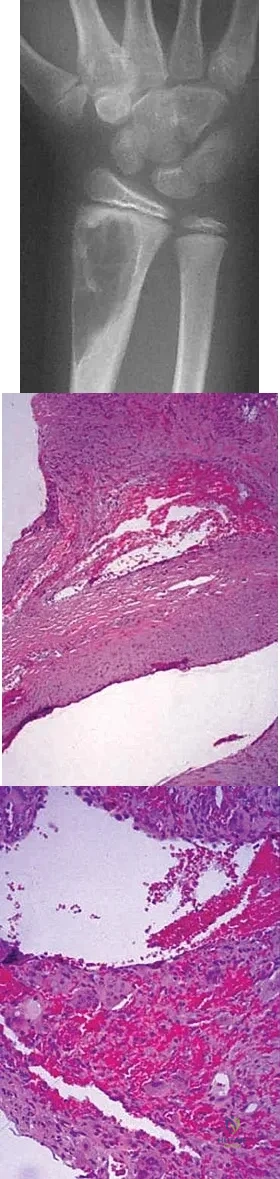

A 40-year-old man has a painless mass around his left ankle. He notes minimal growth over the past year. An MRI scan is shown in Figure 73a, and biopsy specimens are shown in Figures 73b and 73c. What is the most likely diagnosis?

Explanation:

The biopsy specimen is a low-power view of a soft-tissue sarcoma with a biphasic pattern of epithelial cells and fibrous spindle cells that are typical of a synovial sarcoma. A deep, painless soft-tissue mass greater than 5 cm in size is suspicious for a sarcoma. The imaging in this patient is indeterminate and the patient requires a biopsy for an accurate diagnosis. The biopsy reveals a tumor with a biphasic appearance consistent with a synovial sarcoma. These tumors are slow growing, occur primarily in the lower extremities, and are found in a younger demographic population compared to malignant fibrous histiocytoma and liposarcoma. They can occur in a biphasic pattern with clumps of epithelial cells and fibrous spindle cells or in a monophasic pattern. Synovial sarcomas stain positively for keratin. Keratin is positive in nearly all biphasic types and in many tumors of the monophasic fibrous type. Sixty percent of these tumors are found in the lower extremity. The area around the knee is the most common location, followed by the ankle and foot. Epithelioid and clear cell sarcomas are found associated with tendon sheaths of the hand and feet and are generally smaller in size. Epithelioid sarcoma may resemble granulomatous inflammation histologically; clear cell sarcoma is composed of nests of clear cells with occasional multinucleated giant cells. Pigmented villonodular synovitis is found within the synovium and is characterized by a villous histologic appearance with hemosiderin-laden macrophages. Malignant fibrous histiocytoma has a storiform histologic pattern with an abundance of pleomorphic cells. Enzinger FM, Weiss SW: Soft Tissue Tumors, ed 3. St Louis, MO, Mosby, 1995, p 757.